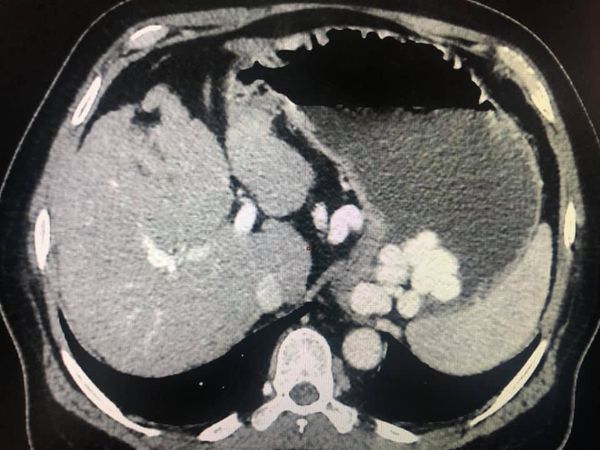

Child’s A CLD with HUGE gastric varices uncontrolled by Endoscopic glue and attempted EUS coiling. One salvage option would be TIPSS with balloon vascular occlusion but due to logistics we went for modified sugiura procedure. Splenectomy + Gastro esophageal devascularisation with anterior Gastrotomy and overseeing of gastric varices with pyloroplasty. Images show 1 CECT showing large gastric fundal varices. 2,3,4 Gastro Esophageal devasc 5, 6 Large fundal varices before and after oversewing. 7. Anterior gastrotomy 8. Pyloroplasty. Postoperative recovery was uneventful.